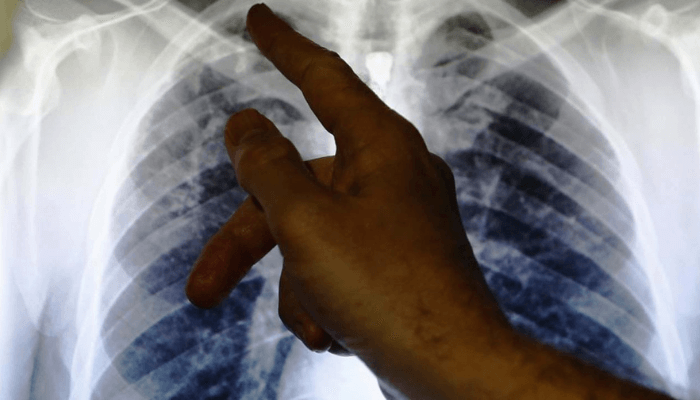

For Iniobong Mkpa, a 53-year-old man in one of the communities with high TB cases, though he has been coughing for more than two weeks, he would rather choose to live with this nagging cough than to provide a sputum for a Tuberculosis (TB) test.

Nigeria ranks 6th among the 30 high burden countries and the first in Africa in terms of numbers of people with TB and every year, around 245,000 Nigerians die from TB and about 590,000 new cases occur, according to the World Health Organisation.

Finding new cases of the disease is important because it will help in bringing them under treatment and reducing the possibility of new infections. To achieve this, many states were given targets to meet.

For instance, Akwa Ibom State had a target of 3085 cases to be found between April and June this year but only 1472 or 47.7percent cases were found, a far cry from the expected target.

“Akwa Ibom State is under-tested; we need people to come out for testing, we are not testing enough to find more cases of TB,” says Bassey Akpan, a medical doctor and the programmes manager, TB and Leprosy Control Programme in the state Ministry of Health.

According to experts, stigmatisation, low microscopy testing for follow up and inadequate funding are some of the challenges hindering the scale up of testing and the finding of new TB cases in addition to “optimisation of sensitisation testing and enrolment of cases during the National Tuberculosis Week marked yearly in March 24.

This shows the critical role of laboratory scientists in chasing the missing TB numbers as any delay in the delivery of the samples, timely testing and submission of results lead to not achieving the overall goal of reducing the disease burden in the state.

According to Benedict Etuk, a laboratory scientist and quality assurance expert, there is need to improve on universal testing to ascertain the status of persons while emphasising the need for proper documentation and labelling of samples collected for testing.